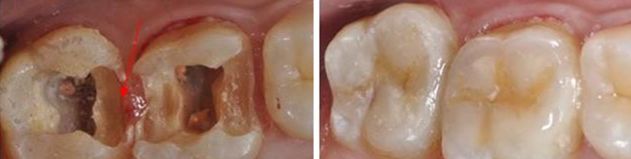

補(bǔ)一顆牙的價格在500元-1000元之間。補(bǔ)牙后24小時內(nèi),補(bǔ)牙側(cè)勿咀嚼硬物。不適癥狀多屬正常反應(yīng),一般可自行緩解。補(bǔ)牙后數(shù)日至數(shù)周內(nèi),有輕微冷熱敏感或咬合不適癥狀多屬正常反應(yīng),一般可自行緩解。補(bǔ)牙后應(yīng)避免食過燙、過冷或較硬食物、以防刺激牙髓和充填物脫落。深齲患牙補(bǔ)牙后如出現(xiàn)敏感癥狀長期無好轉(zhuǎn)或有疼痛加重等情況,需及時聯(lián)系復(fù)診采用根管治療術(shù)繼續(xù)治療。